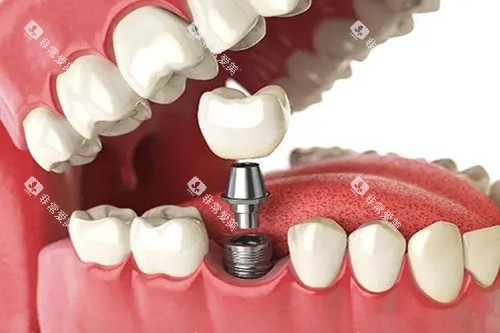

重庆美奥口腔医院涵盖了口腔种植、口腔正畸、牙齿修复、牙齿美白、儿童口腔等多个领域的诊疗项目。

例如,在口腔种植方面,医院采用靠前的种植技术和优质的种植体,为缺失牙患者修复牙齿功能和美观;在口腔正畸方面,提供传统金属矫正、陶瓷矫正、隐形矫正等多种矫正方式,满足不同患者的需求。